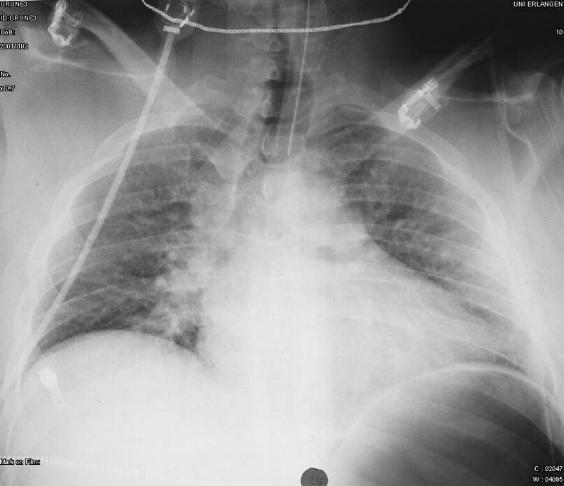

männlich, 33j

• Polytrauma

männlich

• koronare Herzkrankheit

• Herzinsuffizienz NYHA III

• Z.n. Myokardinfarkt

• Z.n. ACVP-Operation

• instabile Angina pectoris

• arterielle Hypertonie

• Diabetes mellitus Typ 2

• plötzliche Luftnot/ Orthopnoe

Röntgenbefund:

• AP-Aufnahme

• Aufnahme verdreht

• Lungenmarkierungen nicht bis an die Thoraxwand sichtbar

• ZVK nicht zentral liegend

Diagnose:

• Pneumothorax beidseits!!